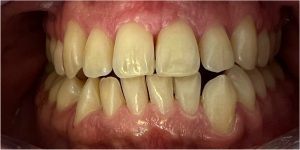

zwężone łuki zębowe,

tyłozgryz,

głęboki zgryz,

stłoczenia,

zrotowane i starte zęby

Pod opieką Agnieszki Łukowicz, Master of Science Orthodontics została poddana zaawansowanemu leczeniu aparatem stałym ligaturowym, Dzięki czemu udało się osiągnąć znaczące zmiany:

poszerzenie luków zębowych,

korekta tyłozgryzu,

rozwiązanie stłoczenia,

odrotowanie zrotowanych zębów,

odbudowa startych zębów.

Efekt estetyczny został dopełniony przez wybielanie zębów i odbudowę kompozytową wykonaną przez dr Monikę Niewitecką.

Przedstawiamy piękny i zdrowy uśmiech naszej Pacjentki!